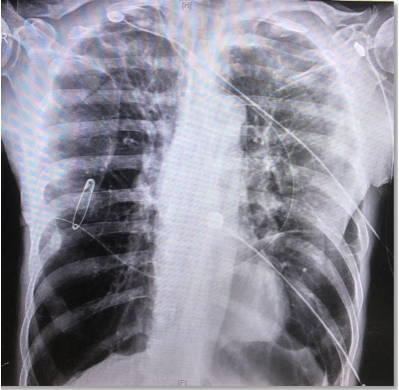

患者男性,65岁,肺鳞癌,气管中段外压性狭窄,气管金属支架置入术后13天,胸闷气急进行性加重,端坐位,指脉血氧饱和度80%~85%。

图片

支架植入术后7天,肿瘤已长入支架腔,清理后缓解。